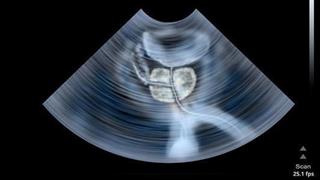

Καρκίνος προστάτη

Καρκίνος προστάτη: Γιατί να προτιμήσω τη ρομποτική χειρουργική;

Παρόλο που ο προστατικός καρκίνος είναι μια σοβαρή ασθένεια, οι περισσότεροι άντρες επιβιώνουν, ιδιαίτερα όταν αυτή ανιχνευθεί σε πρώιμο στάδιο